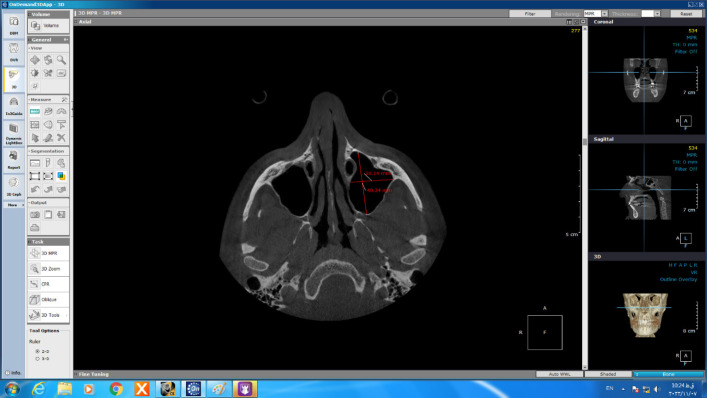

Methods: CBCT records taken during 2020-2022 of 120 patients were obtained to investigate the relationship between impacted canine and maxillary morphology as well as sinus dimensions. The CBCT images were then divided into three groups: control, unilaterally canine impaction and bilaterally canine impaction. Then morphology-related variables (arch circumference, arch length, inter molar width, inter first premolar width, palatal depth, anterior posterior dimension of the right and left sinuses, and mediolateral dimension of the right and left sinuses) were analyzed and compared between groups. All measurements were done by Ondeman 3D dental software. Statistical analysis was carried out by SPSS software version 21 using one-way ANOVA.

Results: There were meaningful differences in patients with canine impaction compared with control group in arch circumference (P value= 0.004) and arch length (P value= 0.001), inter molar width (P value= 0.001), inter first premolar width (P value= 0.001), mediolateral dimension of the right (P value=0.001) and left (P value= 0.001) sinuses of maxilla. Furthermore, Palatal depth and anterior posterior dimension of the right and left sinuses did not show statistically significant difference between groups.